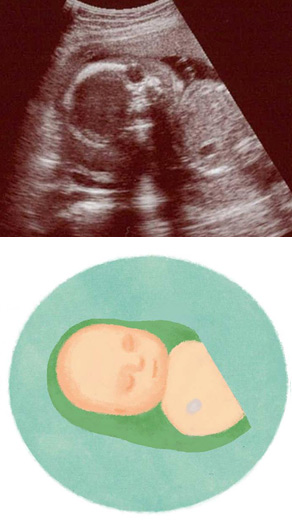

妊娠22週ころの超音波写真

鼻の骨など部位の発達も顕著になります

赤ちゃんが大きくなり、上半身しか写り込まなくなりました。黒くくぼんだ部分が目。鼻の骨が白く鮮明に。なお、超音波では、骨が強く白く写り込んだ下側は、黒く出る傾向があります。